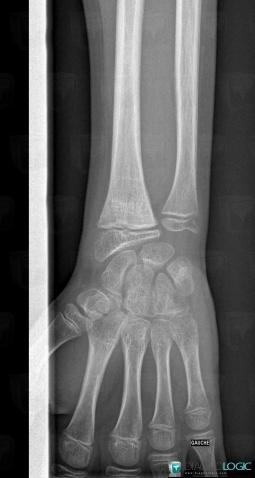

Fracture, Radius - Distal part, X rays

Here is the specific information in the key image above:

- Diagnosis Fracture, Location(s) Radius - Distal part, with gamuts